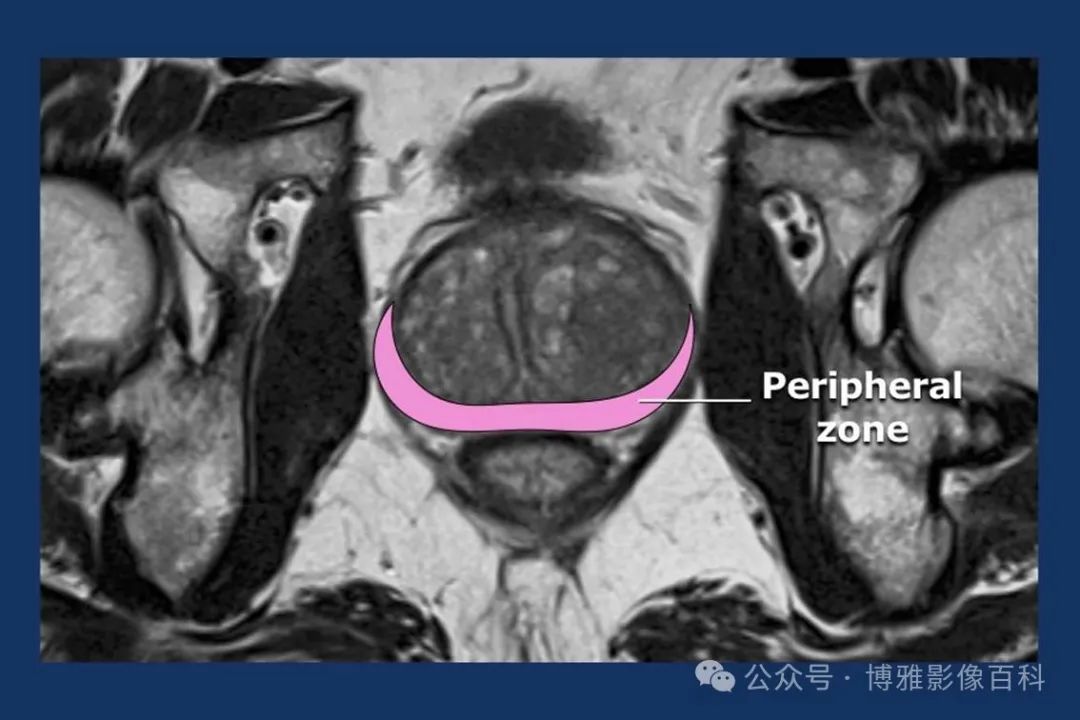

70-75% 的前列腺癌起源于外周带 (PZ)。该区域的后部可以通过直肠指检进行检查。

MR 解剖学

前列腺良性增生患者的轴向T2 图像,其他方面正常。外周带是一薄层均匀的高信号,边界清晰连续性的低信号包膜。移行带通常表现为不均匀中等信号,病灶被边界清楚的BPH良性前列腺增生结节所取代。精囊具有均匀T2高信号。未见淋巴结肿大。